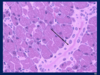

Explain the image

Photomicrograph of centrilobular necrosis in human liver. This photomicrograph shows a routine H&E liver biopsy specimen from an individual with congestive heart failure. Pathologic changes (referred to as ischemic necrosis) are most severe in hepatocytes in zone 3. This zone surrounds the terminal hepatic venule (central vein). This type of necrosis is referred to as centrilobular necrosis. Note the presence of multiple round vacuoles, which indicates extensive lipid accumulation. No noticeable changes are seen in the periphery of the lobule, that is zone 1 and much of zone 2